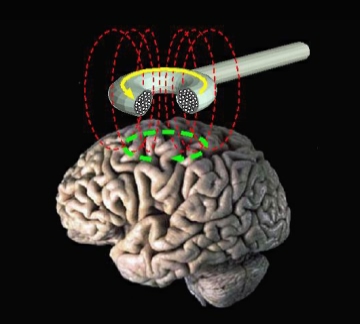

Maar nu lijken Spiegel en zijn collega’s een manier te hebben gevonden om die breininteractie tijdelijk te laten toenemen zodat iemand gevoeliger wordt voor hypnose. Aan hun onderzoek deden tachtig mensen met fibromyalgie, een vorm van chronisch zenuwpijn, mee. De helft van hen ondergingen transcraniële magnetische breinstimulatie (TMS).

Bij TMS wordt een magnetisch veld gebruikt om van buitenaf elektrische pulsen toe te dienen (zie beeld hierboven). Die pulsen kwamen terecht in de dorsolaterale prefrontale cortex. De exacte locatie was afhankelijk van de unieke structuur en activiteit van elke patiënt. De andere helft van de proefpersonen kregen een nepbehandeling die leek en voelde als TMS maar die geen elektrische pulsen afgaf.